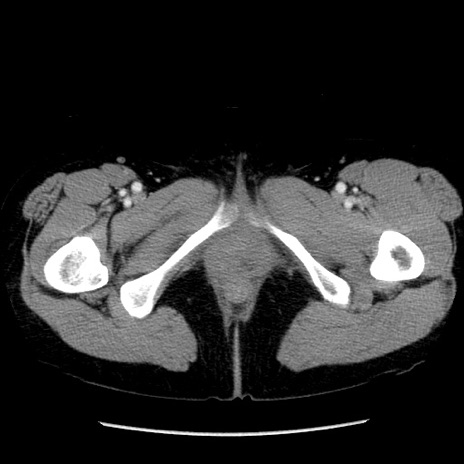

症例6(横断像)

【症例】50歳代女性

【主訴】下腹部痛

【現病歴】本日朝より下痢2回あり。 昼食を食べた後、嘔吐3回、下腹部痛認め、症状軽快せず、当院救急搬送。

最終食事:本日昼(生ものなし)。 昨日の夜、刺身を食ぺたとのこと。周囲に同様の症状の者なし。普段、排便は毎日あるとのこと。

【既往歴】卵巣癌術後(8年前に当院で卵巣摘出)

【身体所見】 意識清明、腹部:平坦、腸蠕動音→、やや硬、下腹部自発痛・圧痛あり、反跳痛あり、筋性防御なし。

【データ】WBC 16000、CRP 0.01